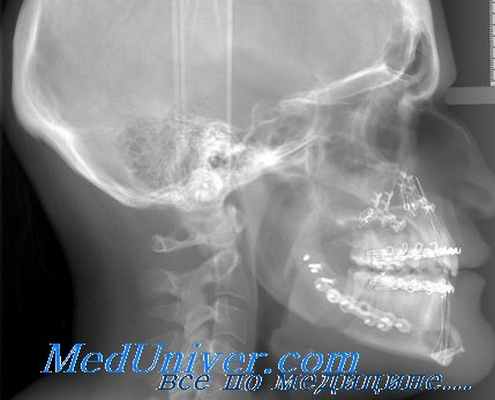

При рентгенологическом исследовании к основным симптомам аденомы гипофиза относят изменение размера и формы турецкого седла, истончение и деструкцию образующих его костных структур. В случае проведения компьютерной томографии можно визуализировать и непосредственно опухоль.

Главный метод диагностики аденомы гипофиза – клинико-биохимическое исследование, а также краниография (рентгенологическое исследование). Кроме того, используют компьютерную томографию, радиоиммунологический метод, ЯМР-томографию. В первую очередь проводится именно краниография в 2 проекциях, а также томография области турецкого седла, позволяющая выявить признаки внутриселлярного объемного процесса, который провоцирует изменения в костных структурах (остеопороз, деструкцию спинки турецкого седла). Характерная особенность – двухконтурность дна в турецком седле. Наличие опухоли, ее структуру, размеры и направление разрастания позволяет определить компьютерная томография (с контрастным усилением). Радиоиммунологическое обследование позволяет определить концентрацию гипофизарных гормонов в сыворотке крови. Это специфичный и высокочувствительный метод определения аденомы гипофиза.

Характерным для рентгенологической картины являются изменения турецкого седла преимущественно на стороне расположения опухоли. При этом отмечается истончение, а иногда и полная деструкция переднего клиновидного отростка. Дно седла на стороне поражения может быть углублено и нечетко контурировано. Также поражается спинка седла и задний клиновидный отросток на соответствующей стороне.

Разницу между одной и другой стороной седла легко обнаружить на прицельных снимках каждой стороны с небольшим фокусным расстоянием. Помогают в этих случаях также снимки с проекцией седла на лобную кость или в большое затылочное отверстие. На таких снимках получается более отчетливое представление о поражении того или другого клиновидного отростка. Можно рекомендовать и стереорентгеиографию области турецкого седла.

При опухолях эндоселлярного типа обычно отмечается равномерное увеличение всех размеров турецкого седла с истончением спинки. Эти опухоли могут расти в различных направлениях, поэтому наряду с увеличением переднезаднего и поперечного размера седла отмечается его углубление (рис. 73). Таким образом, дно гипофизарной ямки опускается в основную пазуху и приближается ко дну средней черепной ямы; в норме, по данным Шуллера, расстояние между ними равно 10 - 15 мм. Спинка седла истончается, удлиняется (за счет опущения дна), выпрямляется, а иногда даже отклоняется кзади. При наличии равномерно увеличенного седла, нечетких контуров его дна и затемнения сфеноидальной пазухи можно думать о проникновении в нее опухоли. Описанная рентгенологическая картина характерна для эозинофильной аденомы (рис. 74), которая наблюдается преимущественно у женщин в возрасте 20 - 40 лет.

а - фотография больной; б - рентгенограмма черепа в боковой проекции, видна интраселлярная опухоль (эозинофильная аденома).

Кроме описанных изменений, рентгенологически в области турецкого седла выявляется утолщение передних клиновидных отростков. Кроме того, отмечается увеличение лобных, решетчатых и гайморовых полостей, утолщение костей свода черепа.

Как видно из описания, акромегалия, которая наступает в результате появления эозинофильной аденомы, имеет очень характерную клиническую и рентгенологическую картину и не представляет затруднений для диагностики.